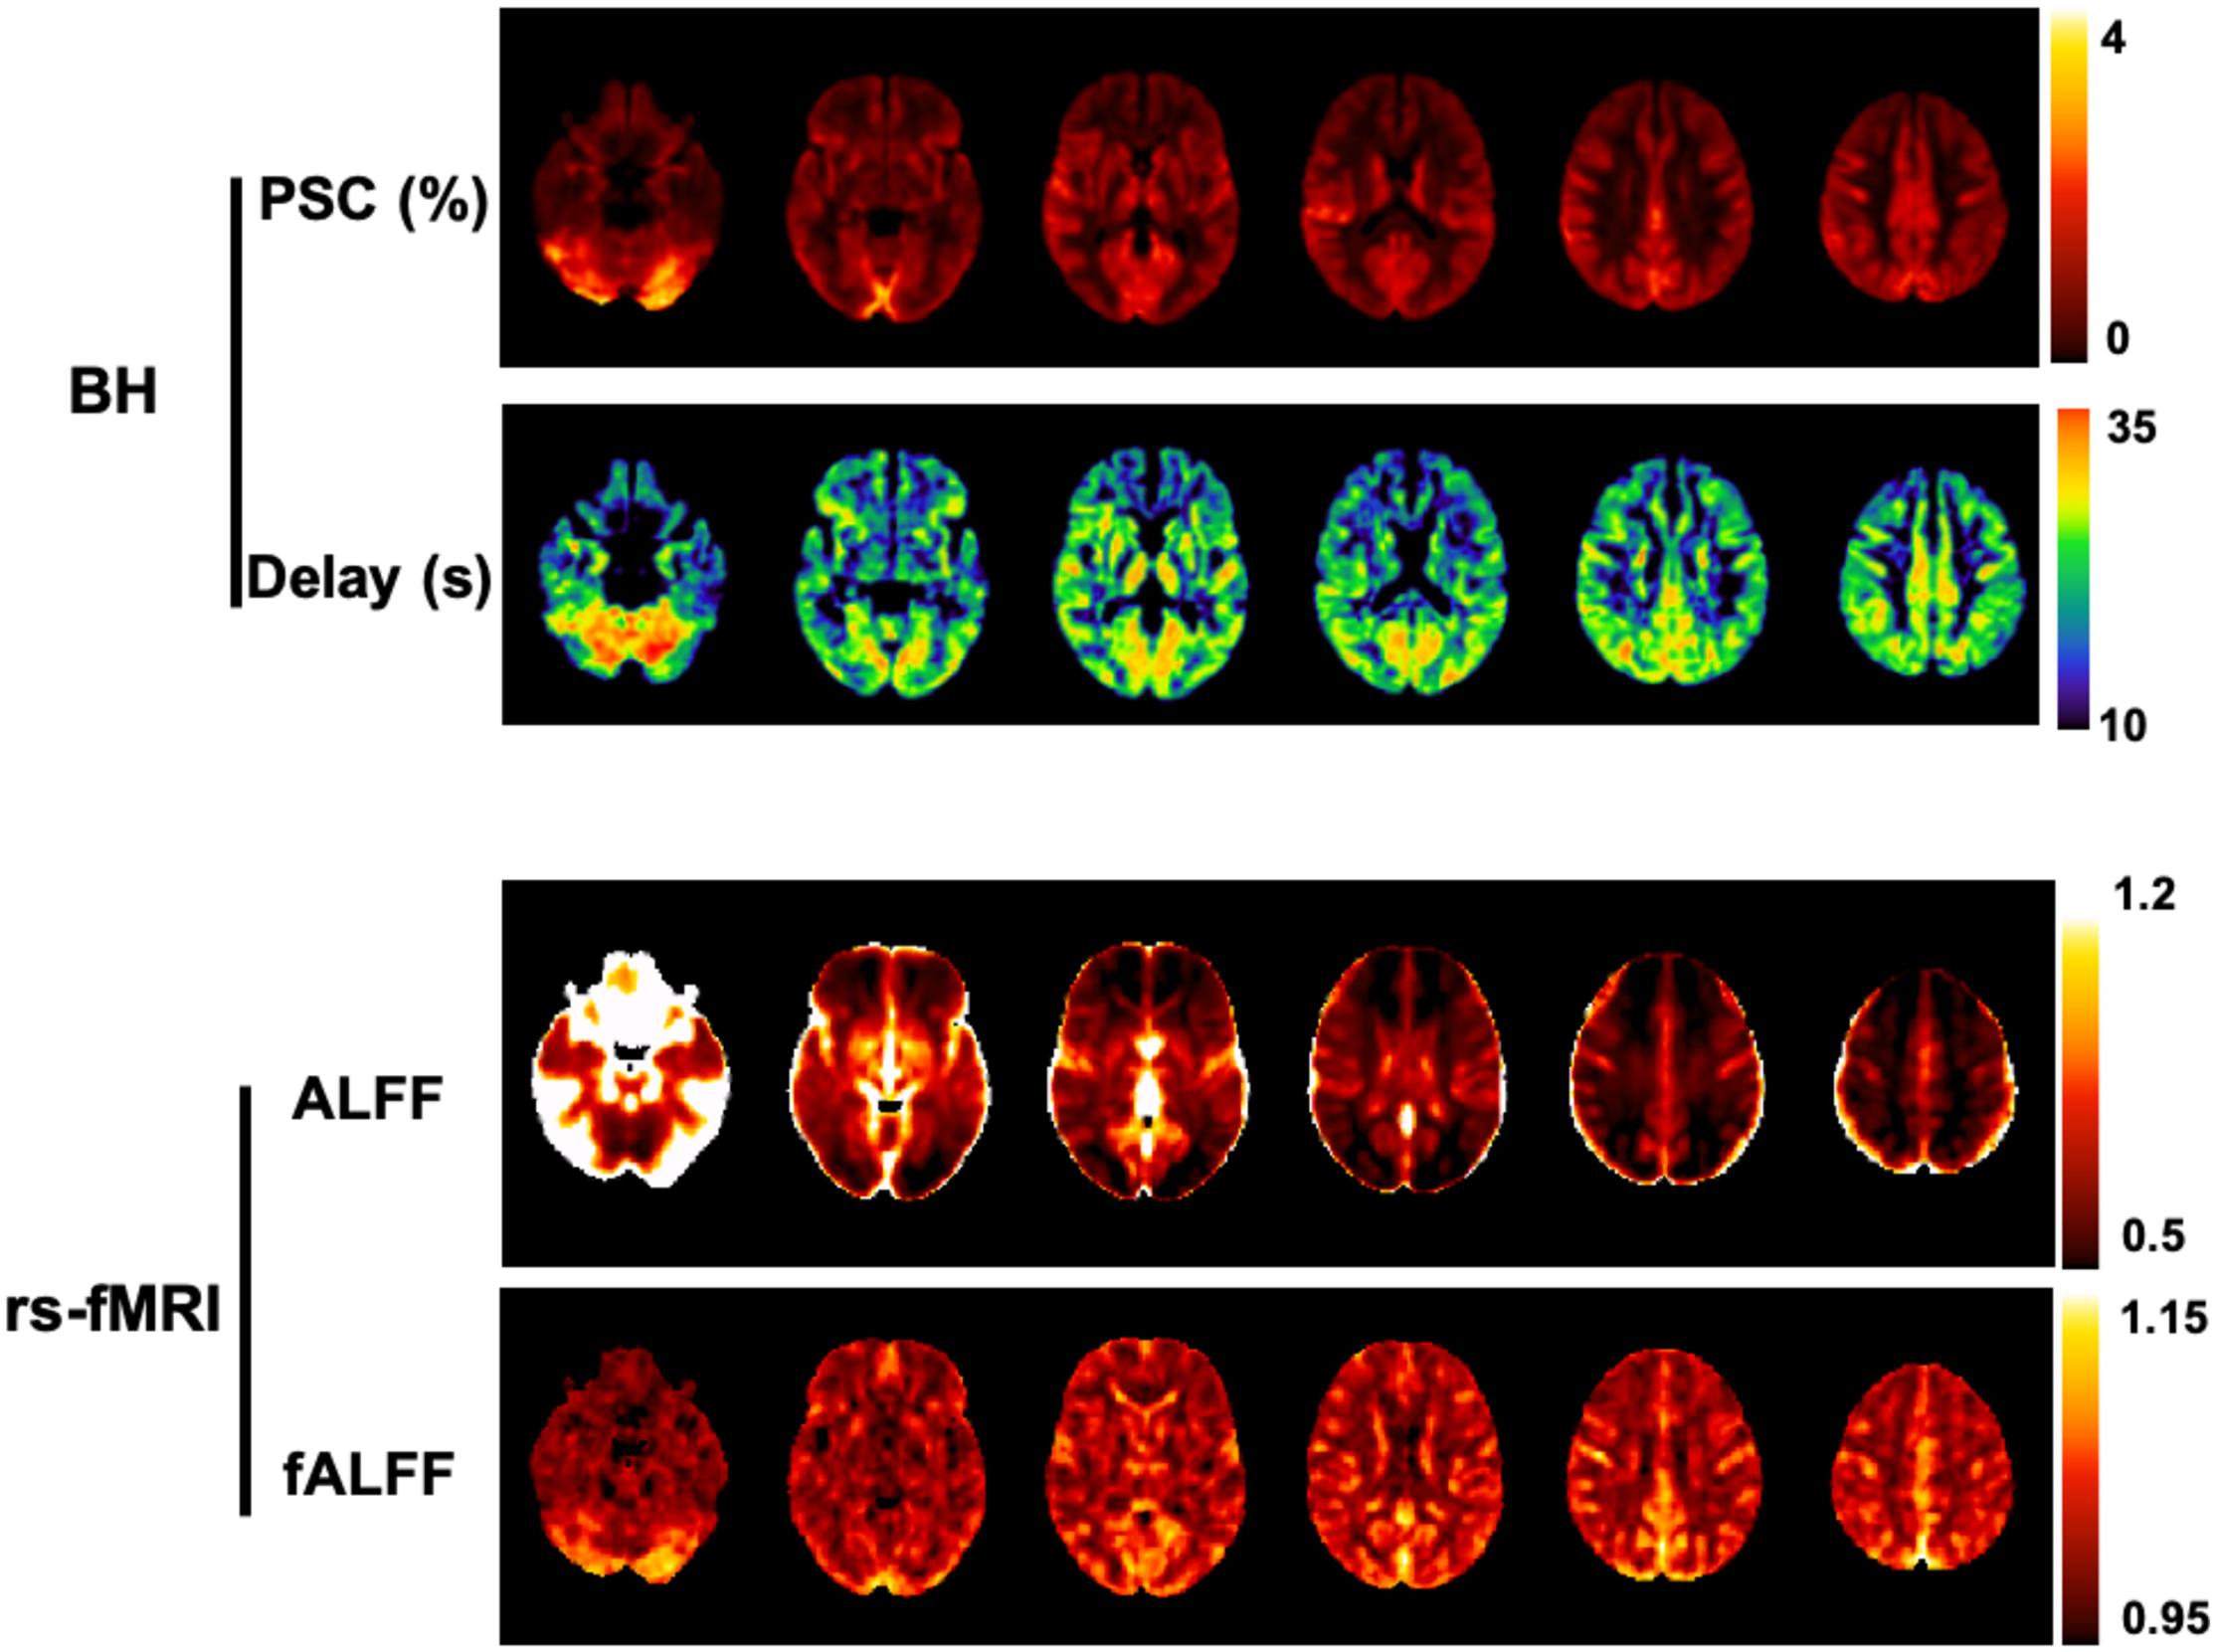

A related metric is the fractional ALFF (fALFF), whereby the power within the low-frequency range is normalized by the power across the whole spectrum (Zou et al., 2008). Both ALFF and fALFF have been shown to yield moderate to high test-retest reliability in gray matter (GM) regions, although ALFF is more reliable than fALFF (Zuo et al., 2010). Nevertheless, it has been demonstrated that ALFF is more prone to non-CVR physiological noise sources in comparison to fALFF, in particular near the ventricles and large blood vessels (Zou et al., 2008; Zuo et al., 2010). In summary, there is a tradeoff between reliability/specificity between the two metrics, and therefore some authors recommend reporting both ALFF and fALFF (Zuo et al., 2010; Figure 4).

Figure 4. Comparison between BH and rs-fMRI protocols: (Top) CVR amplitude and delay maps obtained using BH BOLD-fMRI and the Fourier basis modeling approach (Pinto et al., 2016). (Bottom) Maps of ALFF and fALFF computed in the 0.01 - 0.023 Hz frequency band. All maps are group averages across 12 healthy individuals. For comparison purposes with the rs-fMRI metrics, the CVR amplitude maps are represented in non-normalized units of absolute BOLD percent signal change (PSC).